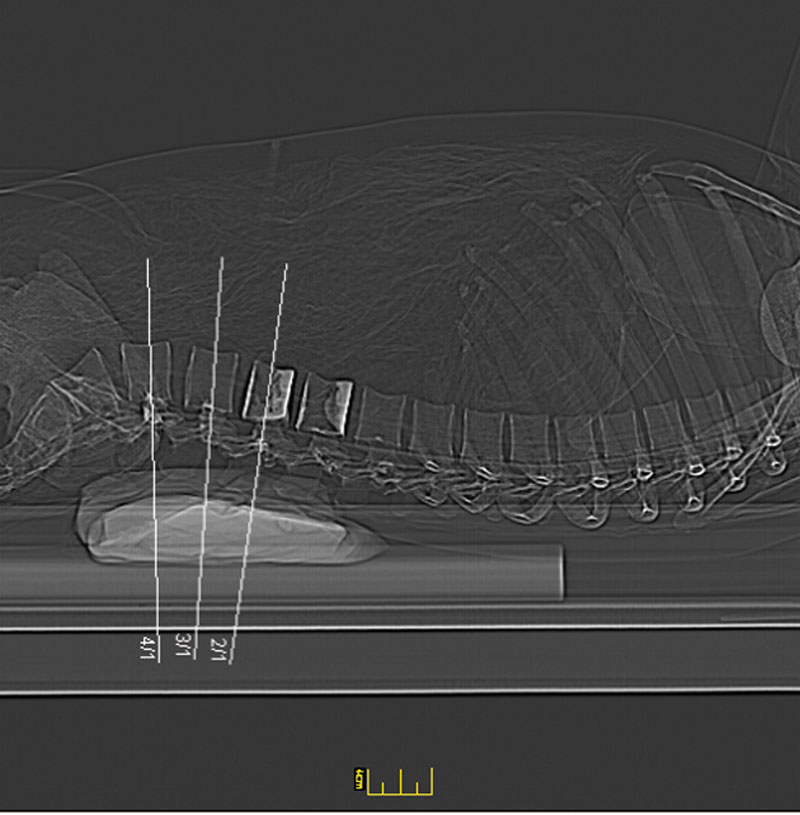

Dieses weltweit einmalige Phantom bietet erstklassige Übungsmöglichkeiten für die Lagerungs- und Einstelltechnik in der Projektions-Radiographie und gehört eigentlich zur Grundausstattung jeder Röntgen-Ausbildungsstätte.

Das Phantom enthält ein natürliches menschliches Skelett, dadurch können mit dem Phantom echte Röntgenaufnahmen wie beim Patienten gemacht werden.

Durch die Verwendung des echten Skeletts können Leitstrukturen im Knochen erkannt werden, was bei Kunststoffskeletten nicht möglich wäre. Bei der Montage des Phantoms wird besonderer Wert auf die Darstellung der Gelenkspalte gelegt.

Die Gelenke sind beweglich montiert und ermöglichen die Lagerung in den normalen Röntgenpositionen.

Die Arme können nach oben bewegt werden, so dass das Modell auch für alle knöchernen Untersuchungen im CT verwendet werden kann. Bei jedem Phantom handelt es sich um ein handgefertigtes Unikat, welches sich in Größe und Ausführung unterscheiden kann.

Je nach Modell können pathologische Befunde vorhanden sein, die äußere Erscheinung kann sich je nach Größe des Modells unterscheiden. Die neue Ausführung dieses Modells wurde in Zusammenarbeit mit einer namhaften deutschen Schule für Med. Techn. Radiologieassistenten komplett überarbeitet und erfüllt alle Anforderungen für die Ausbildung.

Der Verkauf dieses Phantoms erfolgt nur gegen Nachweis der medizinischen Verwendung. Natürliche Größe.

7200

GANZKÖRPER RÖNTGENPHANTOM

24.957,98 € (29700,00 €)